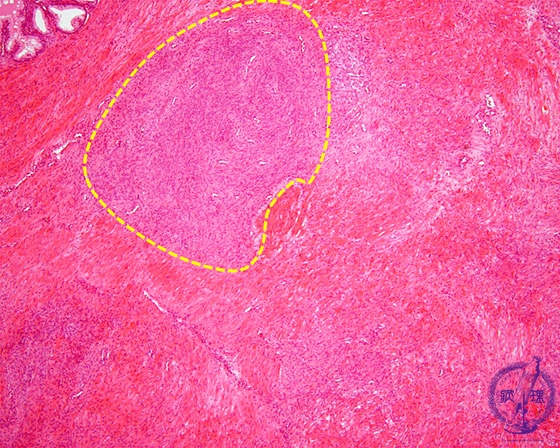

Histology (HE stain, low power): Nodular hyperplasia of interstitial fibromuscular tissue (stromal hyperplasia, yellow dotted line).Compare stromal hyperplasia with glandular hyperplasia.。